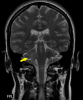

Varón de 38 años, ex-adicto a drogas por vía parenteral sin otros antecedentes de interés, que presenta cuadro progresivo de 3 semanas de evolución de cefalea, fiebre, inestabilidad de la marcha secundaria a torpeza de...

Neurología: InfecciosasEtiología: Infecciosas / inflamatoria / desmielinizanteDiagnóstico final: Toxoplasmosis cerebralNivel de certeza: